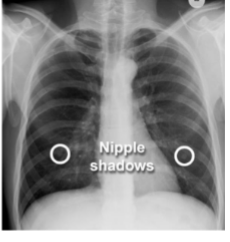

Identify soft tissues/what are you looking for?

nipples

identify nipple shadows

yes